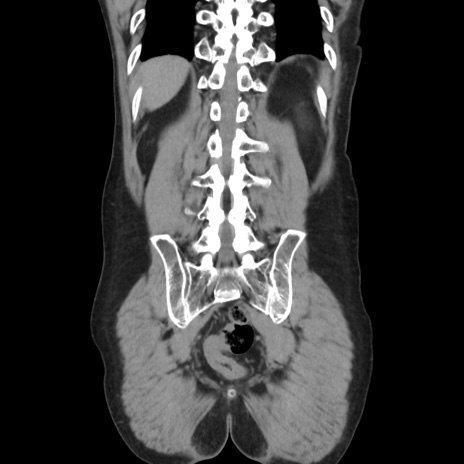

症例37(冠状断像)

【症例】40歳代 男性

【主訴】腹痛

【現病歴】4時間ほど前に電車に乗車中に臍部上より腹痛出現。徐々に増悪し起立困難となり、救急外来受診。生ものは数日食べていない。今朝お雑煮を食べた。

【身体所見】BT 36.8℃、BP 117/84mmHg、HR 91/min、SpO2 97%、苦悶様、腹部:臍上部広範囲圧痛あり、反跳痛±

【データ】WBC 8100、CRP 0.03